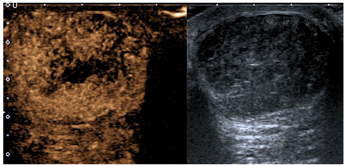

超声造影所见:左乳低回声结节(较大者)呈早期向心性高增强,造影剂灌注不均匀,中央可见不规则片状造影剂无填充区。增强后病灶范围较常规超声无明显变化,边界清晰,形态规则。持续观察3 min,低回声内显影强度始终高于周围乳腺实质。

超声造影提示:左乳多发富血供肿块(BI-RADS 3类,考虑良性病变,纤维腺瘤可能)(图2)。